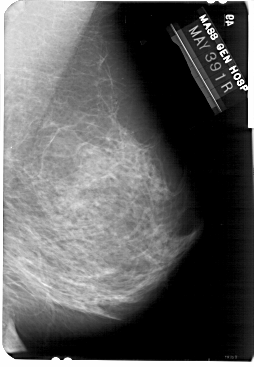

A_1733_1.RIGHT_CC

RIGHT_CC LINES 5491 PIXELS_PER_LINE 3391 BITS_PER_PIXEL 12 RESOLUTION 43.5 NON_OVERLAY